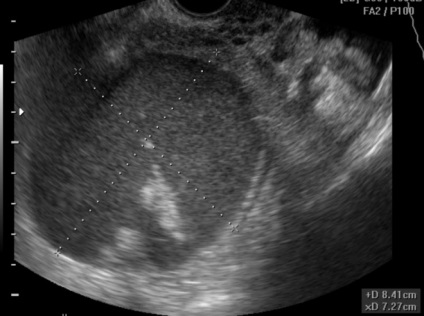

Oldalsó cisztafolyadékban anyagot a bal oldali petefészek-betegség és a szövődmények tartják felbujtóként vagy bakteriális fertőzéses problémákkal. Bal petefészek ciszta, egy fénykép például az általunk a fenti, az esetleges szennyeződések gyakran alakul ki a gyors módon. Az ilyen ciszták hozzájárulhat a tumor megjelenésére és policisztás oldalán. és gyulladást okozhat az urogenitális rendszer és a has.